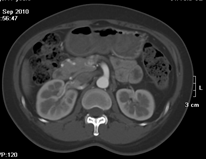

如上圖所示,相鄰的三張軸位圖像未見明顯異常,根據傳統軸位圖像很難得到準確的臨床診斷。

同一病人利用容積數據進行三維處理后,高品質MPR和三維圖像上則清晰顯示了縱向排列的腹腔干與腸系膜上動脈相鄰近,血管發生變 異,近端血管閉塞,為臨床提供了精確的診斷信息。